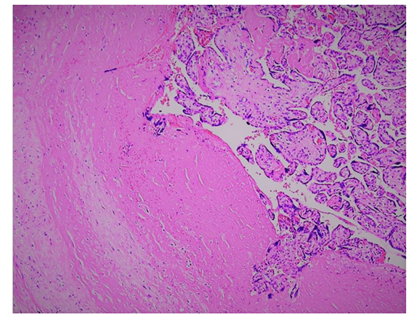

Figure 2 Histological evaluation of uterine tissue revealed placental villi invasion into the myometrium with disruption of the decidual basalis. Note the irregular invasive process which extends into myometrium but no further propagation past this layer.

A 36 yo G4P3003 at 14 weeks 4 days by reported EDD is evaluated within 1 hour of fetus and other passage of products of conception (POC) in her home with presenting symptoms of heavy vaginal bleeding and hypotension with noted vital signs of 80mmHg/40mmHg. Patient was from an outside prenatal facility and did not present with collateral. Past medical and obstetric history was significant for previous three cesarean sections. Upon evaluation the patient received 1000mcg of Misoprostol rectal and the massive transfusion protocol was started with multiple peripheral lines and 3 units of PRBC. Lab work was significant for hemoglobin of 10.9(g/dL) and hematocrit of 30.7%. Coagulation profile of PT/PTT and INR were normal. Once stabilization of patient vital signs with blood and crystalloid; Patient was consented for dilatation and curettage; possible laparotomy and possible hysterectomy. Patient was noted to still be continuously bleeding on passage to OR and while being prepped intra-operatively. During the procedure remaining POC were evacuated and empty endometrial strip was noted on bedside ultrasound, with minimal improvement to brisk and heavy bleeding; prompting the use of additional uterotonics 0.25mg Methergine and 250mcg Carboprost. Despite the continued rescuscitation with ongoing blood transfusion, fresh frozen plasma, platelets, and empty uterine cavity, copious bleeding was noted to be pouring from the vagina and patient vital signs again became hypotensive. The decision was made to proceed with abdominal laparotomy with hysterectomy in order to control hemorrhage. Extensive adhesions were noted from the abdominal rectus to the anterior uterine serosa and bladder. Supracervical hysterectomy was performed and the uterus was found to be atonic; bivalve of gross specimen revealed adherent placenta pathology (Figure 1). Patient was brought to surgical intensive care unit, extubated the following day, with no complications in post-operative course with discharge on POD#3. Patient received in total 7 units of PRBC, 4 units of platelets and 1 unit of fresh frozen plasma. Histological evaluation revealed disruption of decidua basalis with invasion of chorionic villi into myometrium confirming diagnosis of placenta accreta (Figure 2).